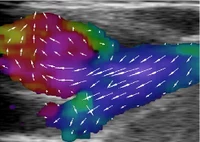

With the new scanner, clinicians and researchers can see 3D images of what is going on inside the body, when it is actually taking place. That is one of the primary benefits of ultrasound - the images are seen in real-time. This for example makes it possible to put pressure on a blood vessel and see how it affects the flow:

- We will use the scanner to develop new ultrasound methods and we are currently developing a new technique to measure the blood's velocity in the body, explains Professor Jørgen Arendt Jensen, Head of Center for Fast Ultrasound Imaging at DTU.